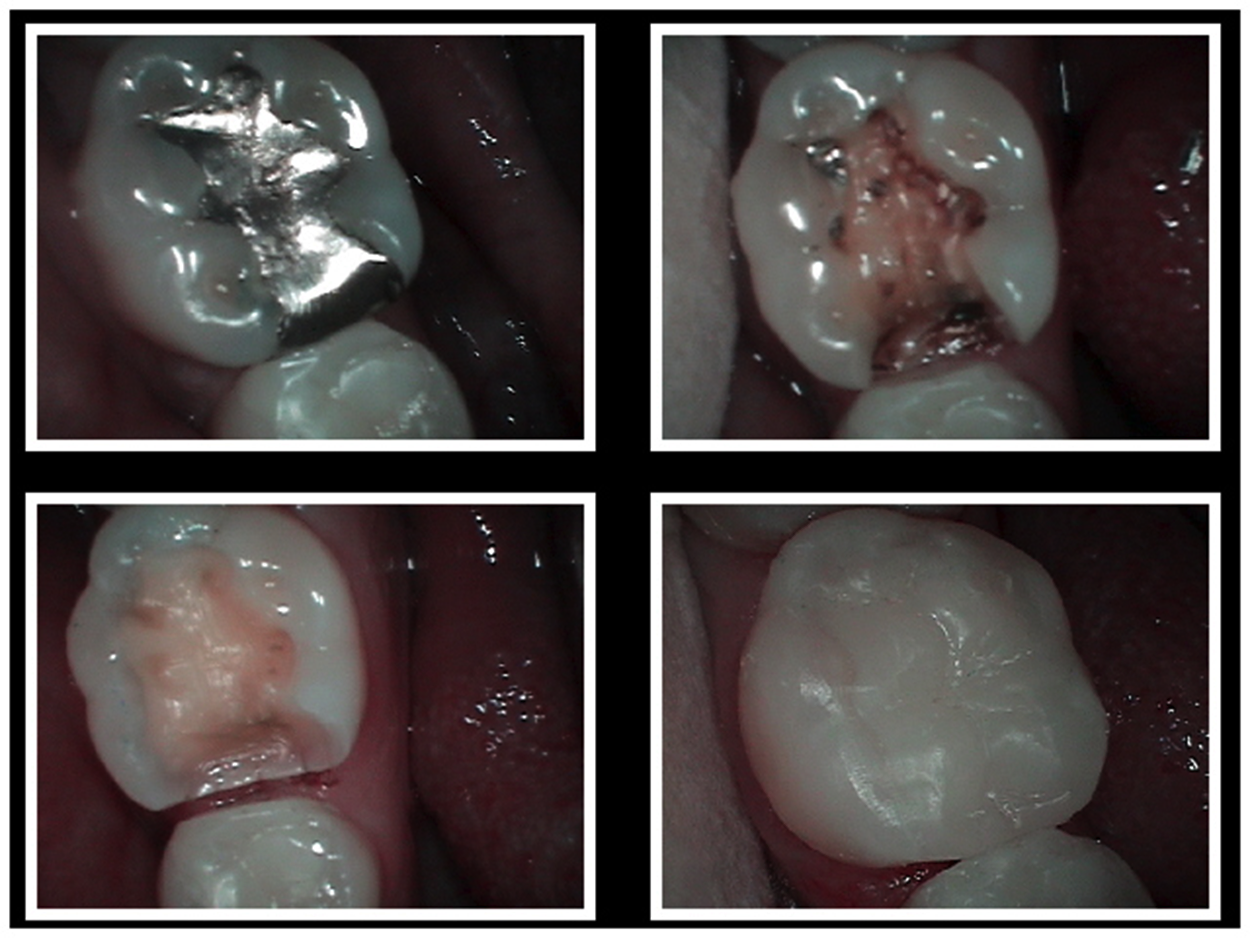

Before & After Amalgam Fillings Replacement Dentist in Merced, CA Mercury In Dental Implants  Studies in the united states, for example, estimate that.  this definitive review explores two critical issues related to the use of mercury in dentistry that have been the subject of.   based on toxicological, clinical, and epidemiological knowledge, the present paper reviews the status regarding.  dental facilities are a significant source of mercury in the wastewater.   there. Mercury In Dental Implants.